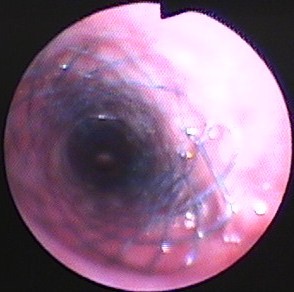

図7 症例1の第475病日。気管支鏡検査所見。ステント前端および内部に反応性肉芽形成。

図8 症例1の第538病日。2週間ごとにマイトマイシンCを肉芽部分に塗布し、肉芽消失。

図9 症例1の第1010病日。アルゴンプラズマ凝固(APC)およびマイトマイシンC(MMC)塗布したが、4ヵ月たつと肉芽再発。

図10 図9と同日、内視鏡で診断後、ただちにAPCおよびMMC塗布し、ただちに気道開存を得た。